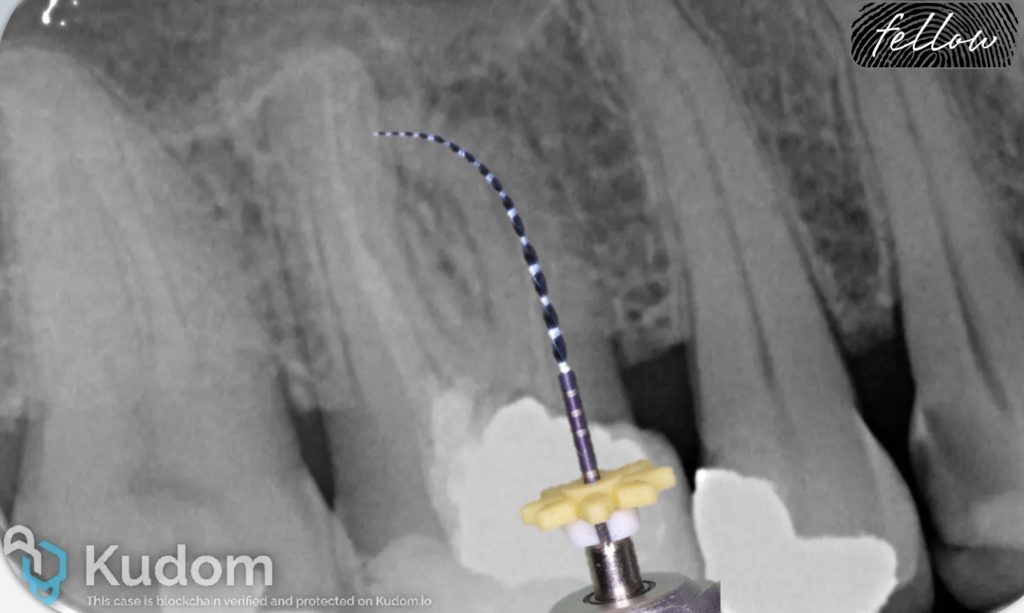

After scouting and coronal preflaring, the file is advanced through the canal using a watch-winding motion. If the file cannot negotiate beyond the curvature, it should be withdrawn 1mm, turned in a new direction with a subtle clockwise motion, and then moved again apically. This step should be repeated until some advancement is made. If the file curvature and the canal curvature (angle of access and angle of incidence) do not match, or the file tip is straightened, apical progress will not be made. The file should not be pushed, but rather withdrawn, recurved, and used again. Many attempts with patience and careful probing might be necessary in challenging cases. As soon as the file tip moves beyond the curvature, it will advance deeper into the canal. At this point, do not withdraw the file to the impediment level, but apply the envelope of motion. The envelope will remove restrictive dentin from the curvature, making it smoother and easier to negotiate. After the curvature is negotiated, the apex locator is used to check whether the terminus has been reached. Upon reaching the WL, the file should not be removed, but used with small 0,5-1mm amplitude coronal-apical vertical strokes, because it may be difficult to reach this point again (6, 12-14).

In the x-ray, the MB1 original canal anatomy could not be negotiated past the perforation, but the curvature was successfully managed in the MB2 canal.